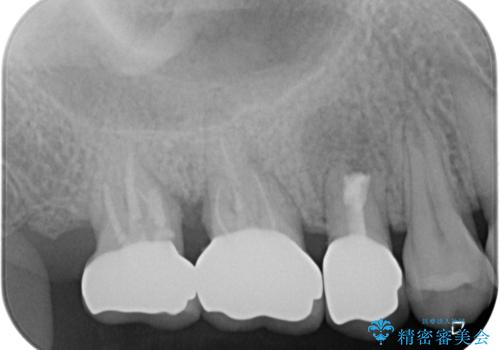

神経近くにまで及んでいる大きなむし歯や、歯肉の中深く、骨の近くにまでむし歯が進行している歯など、問題の多い状態でした。

神経を温存するための処置や、歯肉深くにまで及んだむし歯を改善するための歯周外科処置などを行っていき、オールセラミッククラウンにて補綴治療を行うこととしました。

術前の診断では神経が温存できるか否か、際どい状況でしたが、治療開始前の海外への帰省の際に自発痛(何もしなくてもズキズキ痛む)の症状が出てしまい、根管治療が必要となってしまいました。